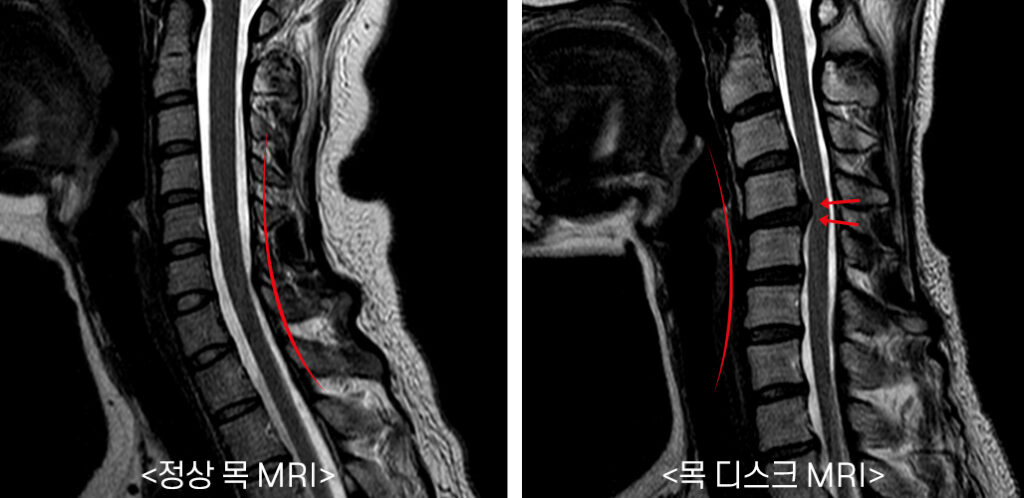

목 뼈와 뼈 사이의 디스크가 제자리에서 이탈되어 신경을 압박하던가 뼈 조직이 비정상적으로 자라 목을 지나는 척추 신경이 눌려 통증을 인지하는 질환이고요.

근골격계질환의 한 가짓수로 그대로 내버려두게가 보면 통증이 점차 더 커지게 된다 하였습니다. 특별히 목은 다른 부위에 비교해서 근육과 인대가 약한편에 속하기에 조심해야 합니다.